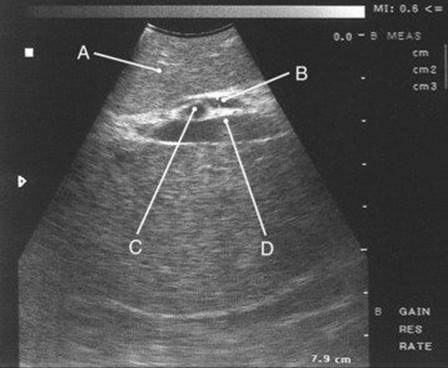

31 A stable patient underwent endoscopic cholangiography following laparoscopic cholecystectomy 2 days previously. What should be done next?

A Endoscopic balloon dilation and stent placement

image

Ref.: 11, 13, 14

Comments

The endoscopic cholangiogram demonstrates complete occlusion of the supraduodenal common bile duct without extravasation of dye. A classic mechanism of major bile duct injury during laparoscopic cholecystectomy involves clipping the distal common bile duct and resecting a portion of the extrahepatic ductal system. The proximal level of injury is variable but typically high. Bile leakage or obstruction occurs, depending on the status of the proximal ducts. The first priority when managing these injuries is to control sepsis and ensure adequate drainage of any bile leak. Generally, this can be accomplished by nonoperative percutaneous or endoscopic methods. Urgent reoperation for bile drainage is not typically necessary. Complete cholangiographic definition of the injury is recommended before definitive repair. For resection or transection injuries, as depicted above, PTC is used to assess the status of the proximal ducts. Endoscopic cholangiography alone may be adequate for lateral injuries when the continuity of the ducts is preserved. Occasionally, a “fistulogram” done through a percutaneous drainage catheter may visualize the proximal ducts. After complete cholangiography, long-term success is best achieved by an elective, expert reconstruction.